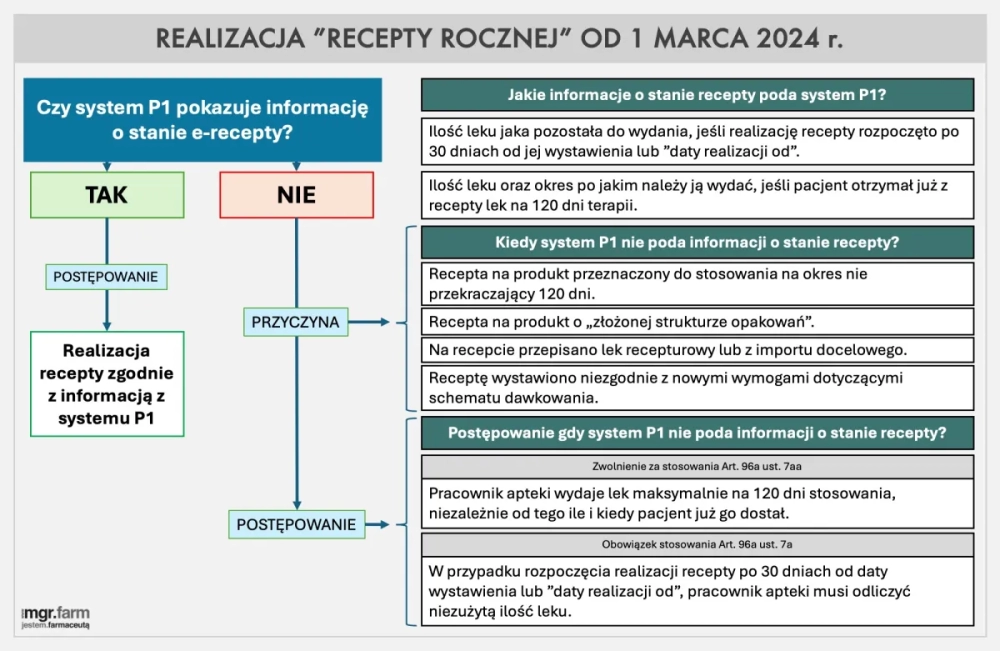

Jak realizować "recepty roczne" od 1 marca? Najważniejsze informacje... - mgr.farm

Jak apteki powinny realizować recepty roczne od 1 marca? System, który ma zacząć obowiązywać od tego dnia zdecydowanie ułatwi pracę...

Recepta od pielęgniarki – ważna 360 czy 180 dni?

„Czy recepta roczna wypisana przez pielęgniarkę może być realizowana w ciągu 360 dni czy 180 dni?”